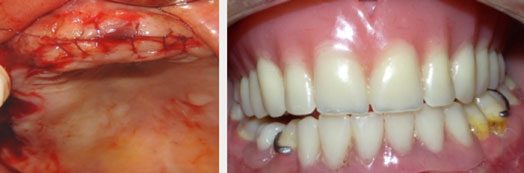

Après réalisation d’incisions intrasulculaires, les extractions ont été faites, la crête alvéolaire régularisée puis les lambeaux vestibulaire et lingual rapprochés à l’aide d’un surjet passé (Fig.14,15).

Fig.14: Régularisation des crêtes après extractions et mise en place des prothèses provisoires. |

Avant Après |

Fig.15 : Sourire de la patiente avant et après réhabilitation prothétique. |